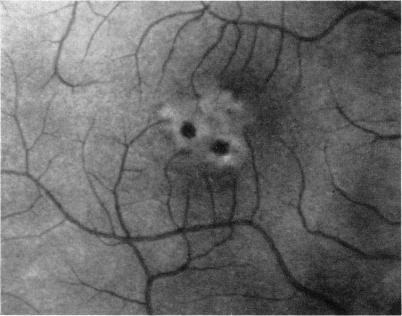

Braley A E, Spivey B E

Trans Am Ophthalmol Soc. 1963;61:339-71.